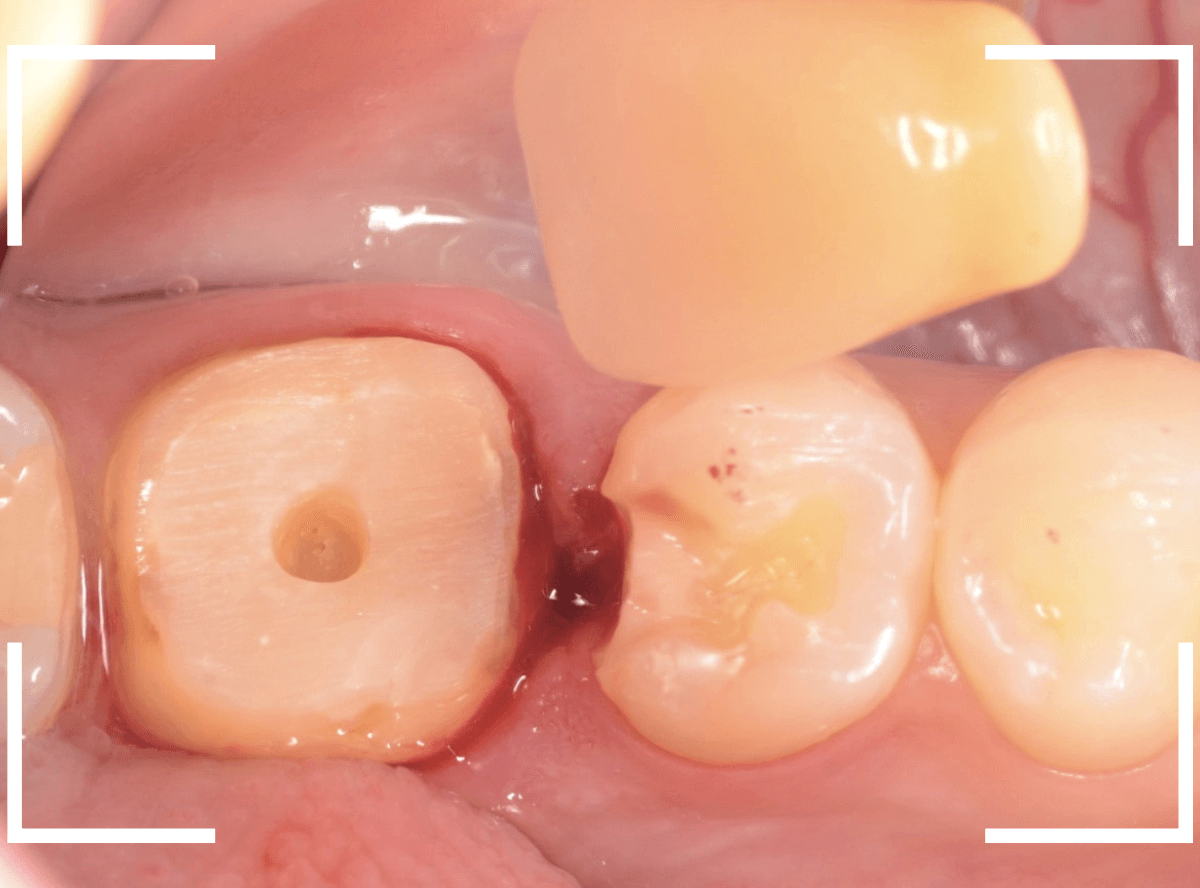

Case.1

大きな虫歯の治療後、オール・ジルコニア・クラウンへ

検診で受診された患者さんです。

過去に治療したセラミック・インレーが不適合になっているのが、レントゲン写真で見つかりました。

初見では特に問題なかったのですが。。。

後ろの歯とのすき間の部分が欠けてしまったのか、不適合になり、中で虫歯が進行しているように見えます。

初めて来院する患者さんや、治療してから年月が経っている患者さんは、定期的にレントゲン写真で確認する事は大事ですね。

セラミックを外して、虫歯を処置したところです。

幸い、中で大きな虫歯になってはおらずホッとしましたが、セラミック・インレーで作り直すのに支えになるエナメル質の部分が薄く、早期に脱落や破折する可能性がある事、また、手前とのすき間に物がつまりやすくなってきたという訴えもありましたので、今回はさし歯(クラウン)に置き換える事になりました。

つめもの(インレー)にするか、思いきってさし歯(クラウン)で対応するかは、まれに悩むケースがあり、意見が分かれるところでもあると思います。

今回は、神経が残っている歯でしたので、つめものからさし歯に置き換える際のデメリットは、歯の削除量が多いため歯がしみる症状が出る可能性がある事です。

しかし、良いさし歯を作るためには、ある程度歯を削り込む必要もあるため、そのバランスが毎回難しいです(絶対に正解はありません)。

仮歯でしばらく経過観察し、症状がないのを確認した後に、型どりをして(オール)ジルコニア・クラウンを製作しました。

お口の中でジルコニアに置き換えた後も、特に症状なく経過されているようで、ホッとしました。